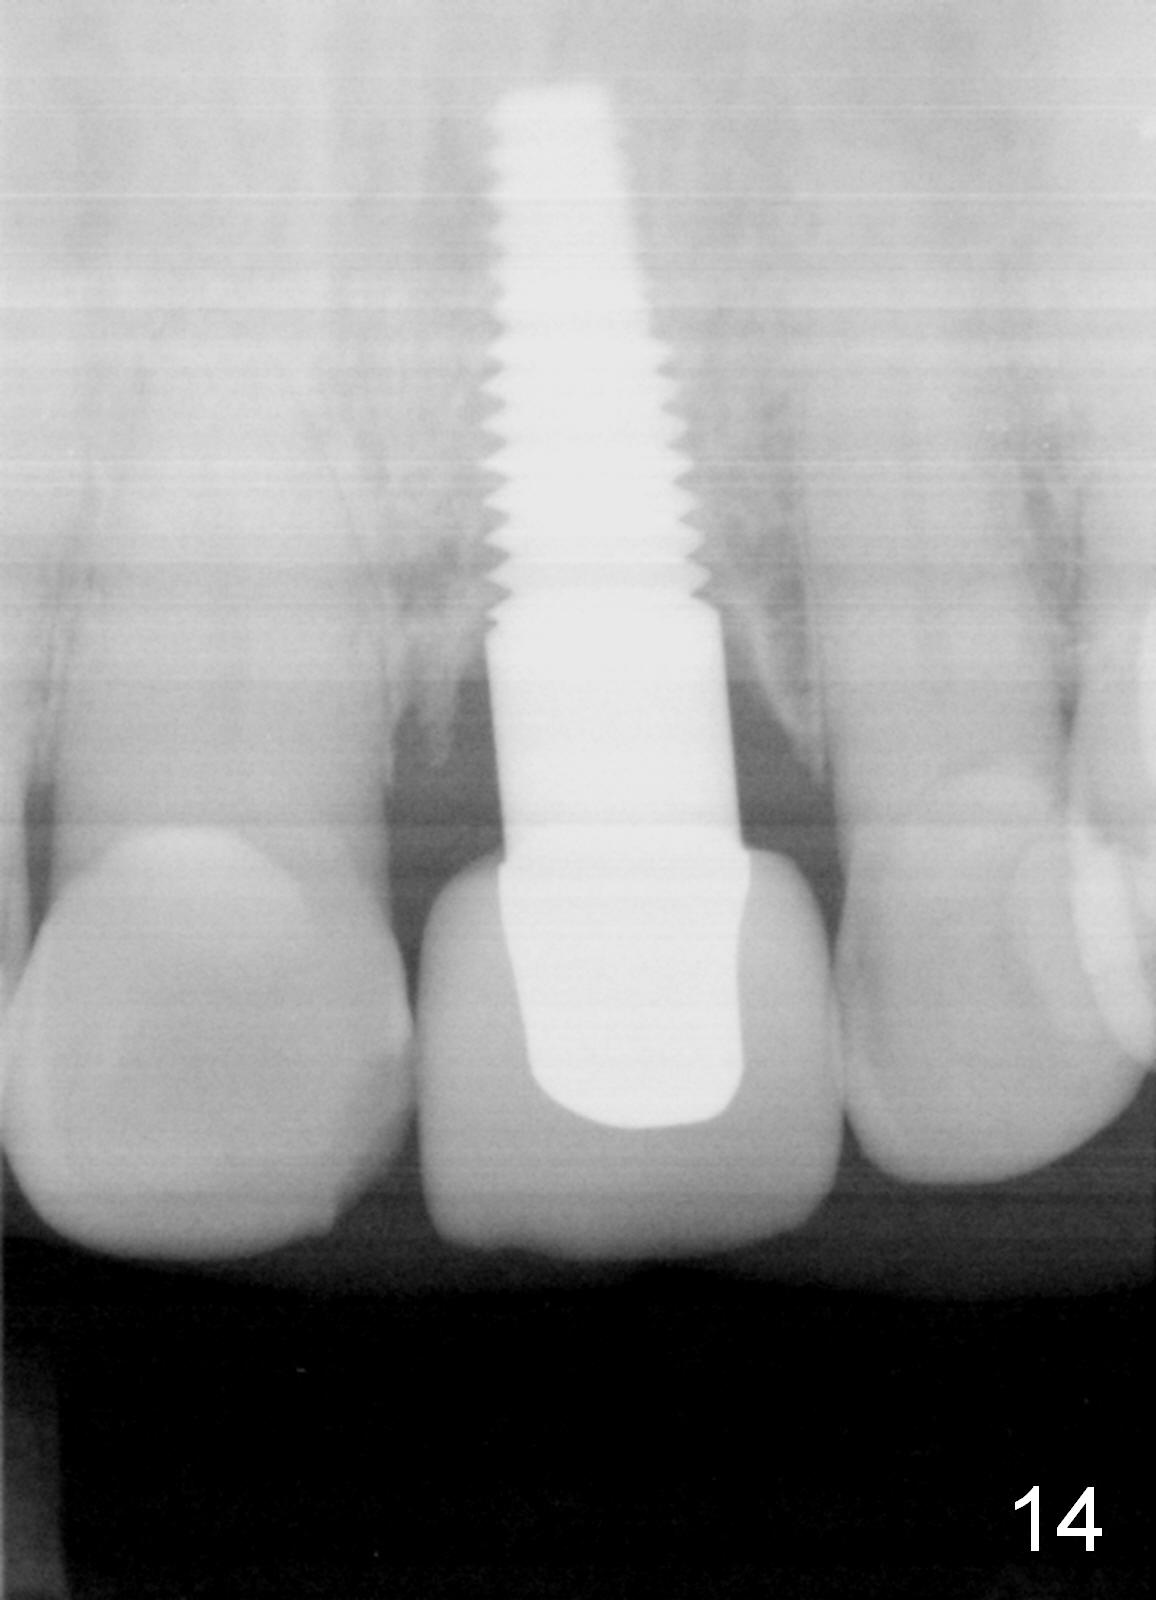

Postop tenderness lasts for two days. The palatal swelling is unnoticeable 7 days postop (Fig.9 *, as compared to A in Fig.8). The bone remains stable around the implant (Fig.10), while the gingiva healthy around the immediate provisional (Fig.11) 5 months postop. Due to insurance limit, the permanent restoration is delayed (16 months postop, Fig.12). The patient is satisfied with the function and appearance 3 years 8 months postop (21 months post cementation, Fig.13,14). PA is taken 4 years 1 month postop (2.5 years post cementation, Fig.15). The lamina dura forms from the most coronal threads (Fig.16). Although there is no bone loss around the implant (Fig.17), metal starts to show 5 years 2 months postop (Fig.18 ^), probably related to the buccal placement, too large the implant for the site or buccal plate atrophy (Fig.19).